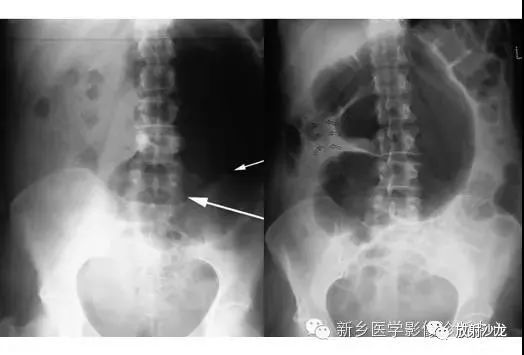

腹痛患者的腹部X光片水平位(左侧)和直立位(右侧)所上图示。是什么原因导致该病人的不适呢?

X线片表现出充满整个腹部的乙状结肠扭转。乙状结肠的两端可以理解成一个倒置的朝向骨盆的U型(图U)。在X光片直立位,可以看出气液平面(箭头)。咖啡豆的标志是乙状结肠扭转的典型的表现。充满气体的肠道包绕重叠水肿的肠壁所形成致密的白线,类似于一个咖啡豆。在这些X光片中,大肠的其余部分均不膨大,大概是因为扭转的点不造成阻塞,从而使消化产物可进入乙状结肠。

逆行通过肛管后所行X光片所示,证明了乙状结肠襻和正常肠道结构压力减低。